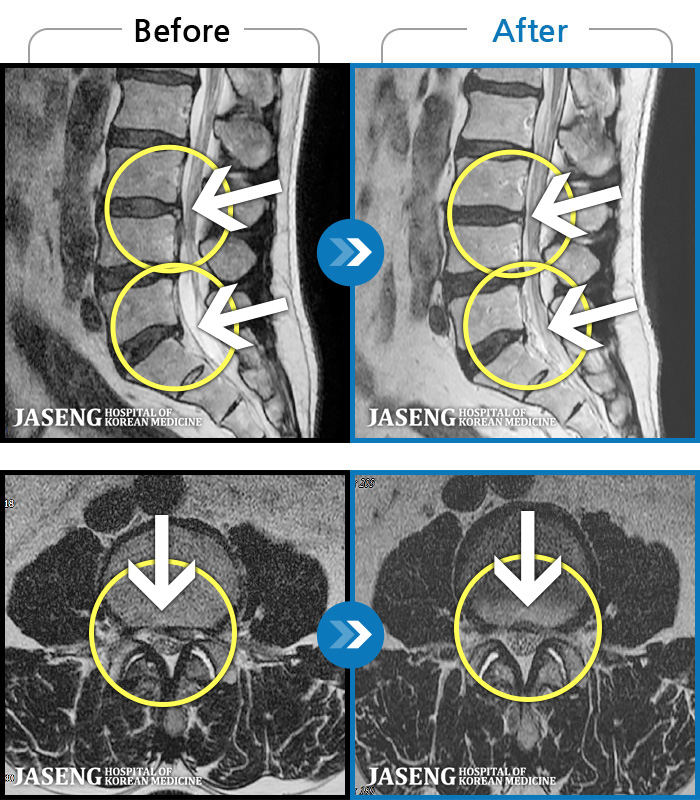

[] 03.04.01~09.11.01